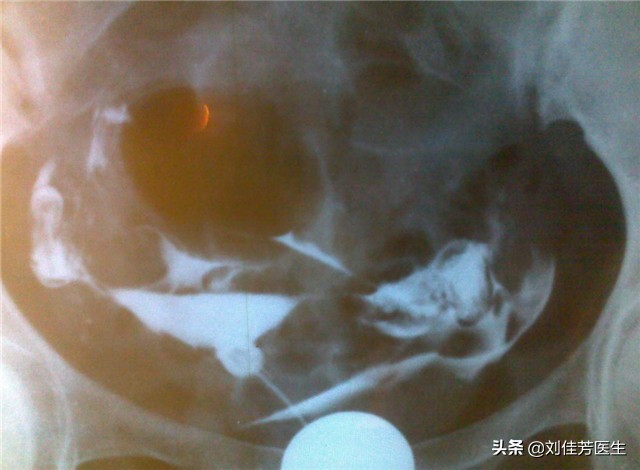

平常生活中,患有这种炎症不通引起的输卵管堵塞的话,会有小腹两侧针扎般的刺痛感。从输卵管造影上,可以看出来,造影是很不均匀的。炎症不通的输卵管堵塞,是最容易出现宫外孕的类型。在中医的治疗方案中,经前要注重活血化瘀,清宫也要重视,同时使用二号热敷药。而在月经经后,治疗措施会有所改变,以消炎为主,凉血为辅。